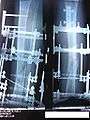

The following case study illustrates the Ilizarov apparatus treatment procedure for a fractured limb. The photographs are of the same patient during the course of treatment.

X-Ray of fracture and initial external fixator applied within 24 hours of patient's admission to hospital

X-Ray of the fracture site immediately following the application of the Ilizarov method

X-Ray of the fracture site, part 1 (two months following fracture)

X-Ray of the fracture site, part 2 (two months following fracture)